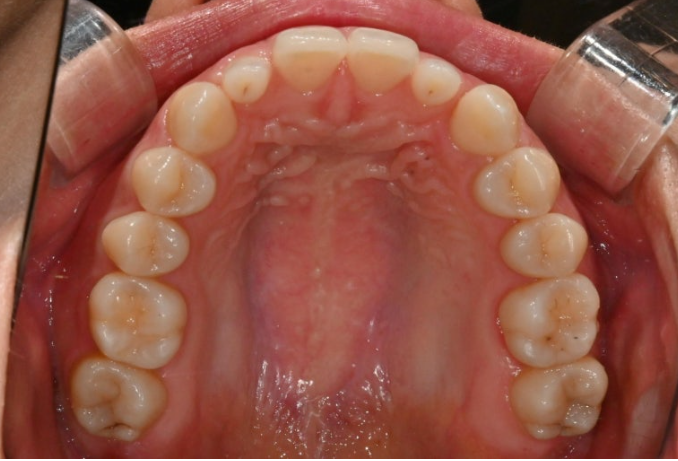

어쨌든 환자분은 치열이나 교합은 완벽하여 별도의 교정치료는 필요가 없는 상태입니다.

다만 앞니 전반에 퍼져있는 흰색 얼룩, 즉 반점치가 있는 상태입니다.